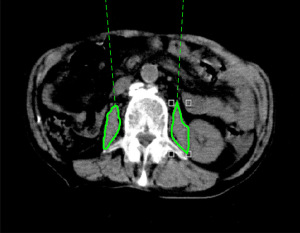

PMI was calculated using CT images taken for diagnosis 1–3 months before RT, CT images taken immediately before RT and used for positioning of irradiation sites during RT planning, and CT images taken for diagnosis 1–3 months after RT. The tracing tool (6) provided in the image viewing system of the CT device was used to calculate the cross-sectional areas of the left and right major psoas muscles at the third lumbar vertebral level. The cross-sectional area of the skeletal muscle was then divided by the height squared. The resultant skeletal muscle index was used for evaluation (Figure 1). Charlson comorbidity index (CCI) (17) and age-adjusted CCI (aCCI) (18) were divided into two categories (CCI: <7 and ≥7; aCCI: <10 and ≥10) for evaluation.